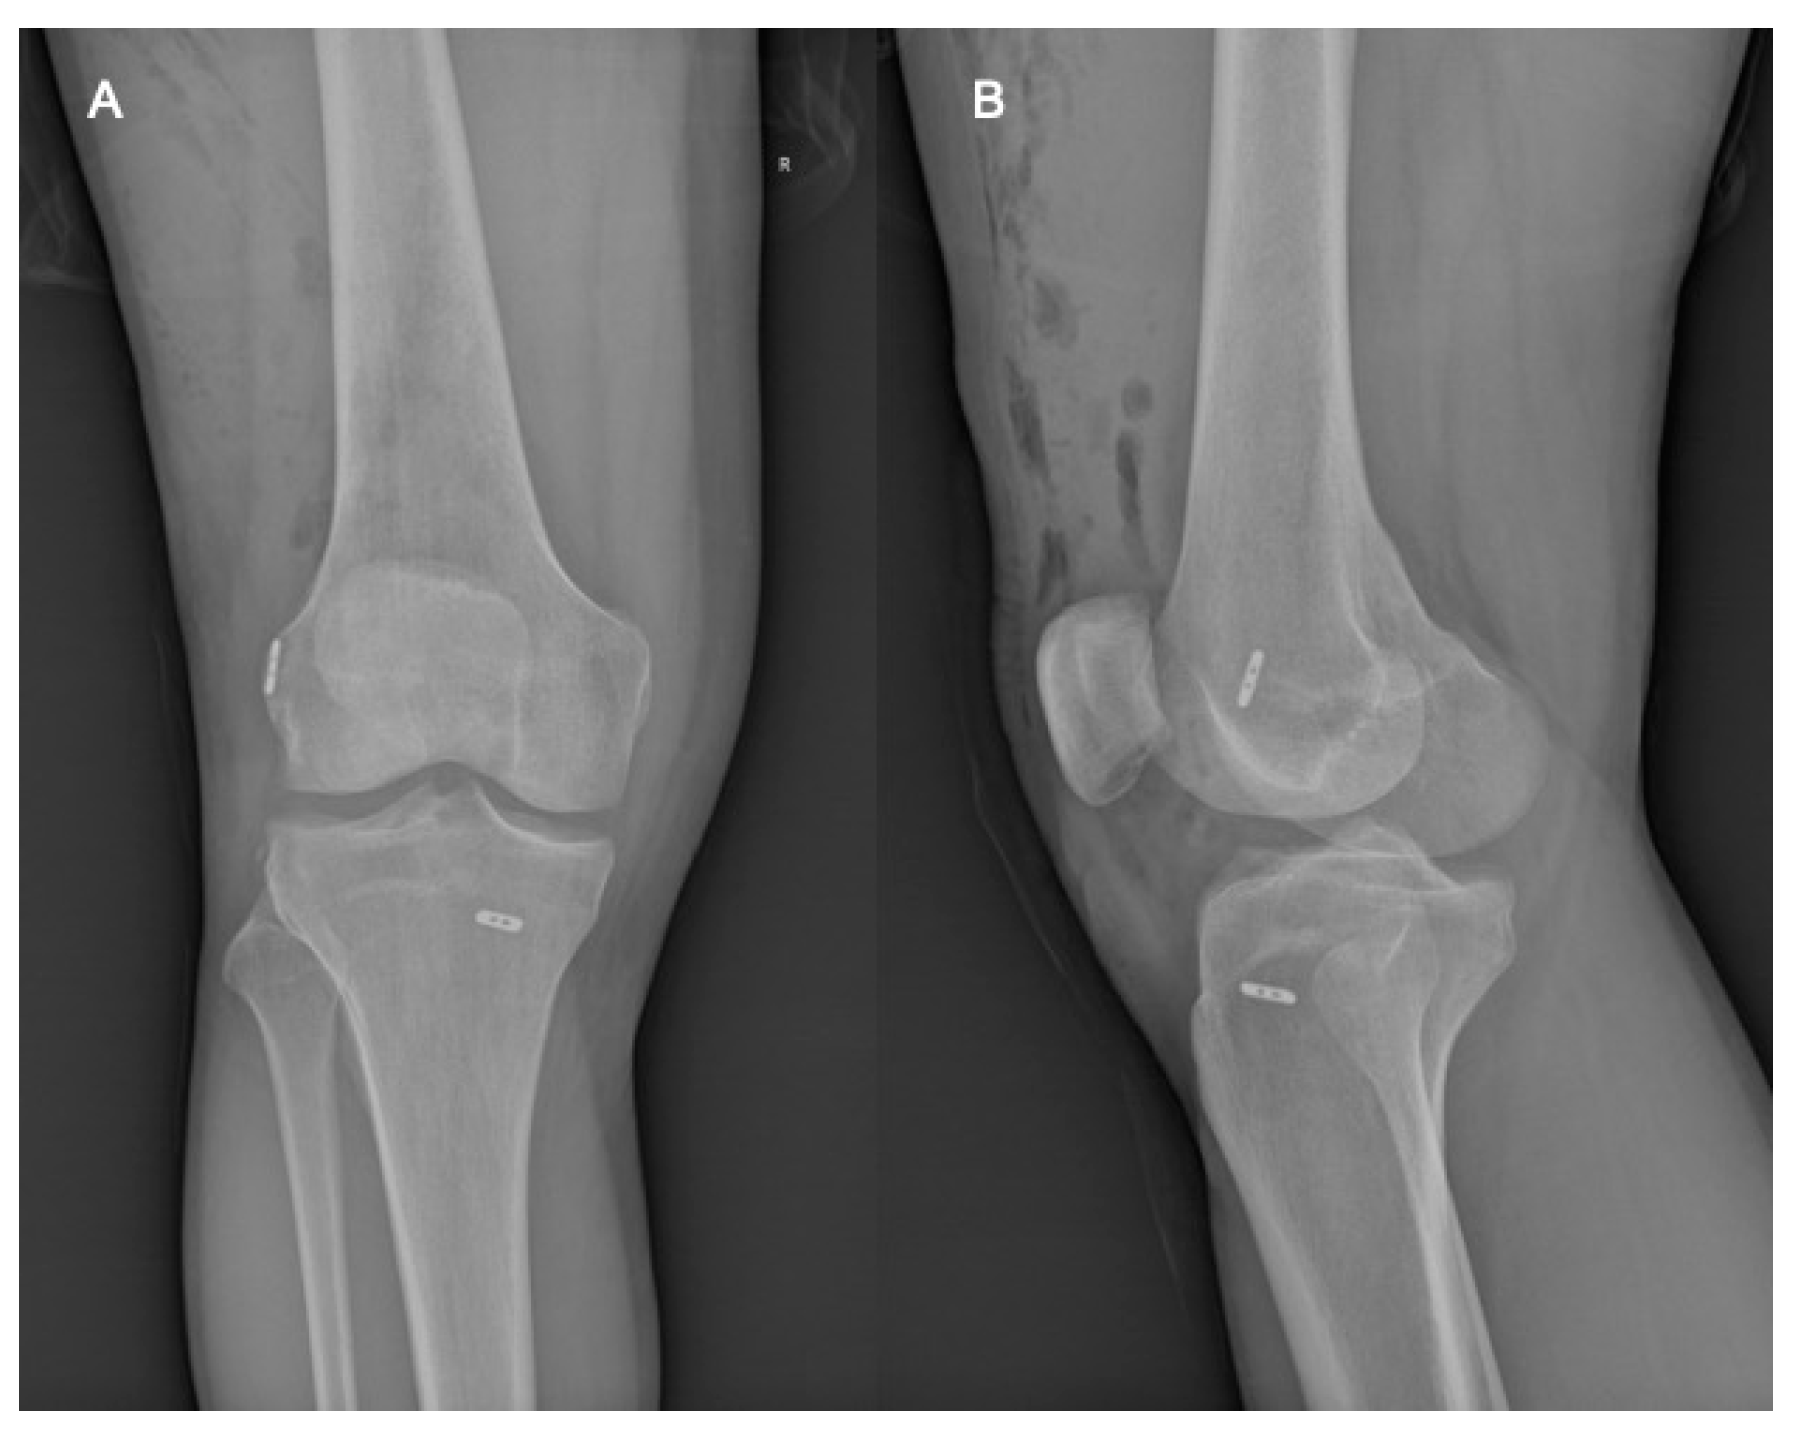

2.2. Surgical Technique